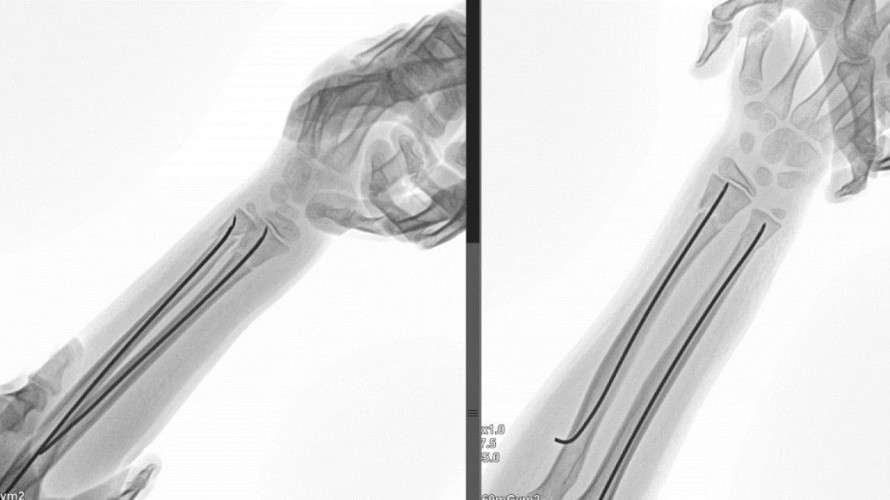

Врачи Ивано-Матрёнинской детской клинической больницы в Иркутске совместно с коллегами из Национального медицинского исследовательского центра травматологии и ортопедии имени Г.И. Турнера в Санкт-Петербурге разработали и внедрили новый метод хирургического лечения одной из самых частых детских травм — перелома лучевой кости в области запястья.

Клиническое исследование, проведённое под руководством директора НМИЦ профессора Сергея Виссарионова и коллектива травматологов иркутской больницы, доказало высокую эффективность технологии. Благодаря её применению частота послеоперационных осложнений снизилась на 80%, а необходимость в повторных хирургических вмешательствах полностью исчезла. Также сократился срок ношения гипсовой повязки — на целую неделю.

Через год после операции у всех 83 юных участников исследования функция руки восстановилась полностью.

Заведующий травматологическим отделением Ивано-Матрёнинской больницы Глеб Большаков рассказал, что новая методика уже внедрена в повседневную практику. Она не сложнее стандартной операции, не требует специального оборудования и обеспечивает детям более быструю и комфортную реабилитацию.